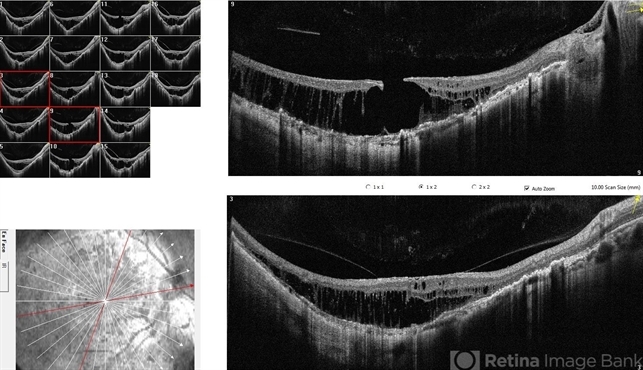

- OCT SURPRISE

- 36 yr old female with recent decline in right eye vision, with left eye having poor vision since childhood. Fundus examination revealed BE healed chororetinitis with RE OCT s/o maculoschisis with full thickness macular hole.